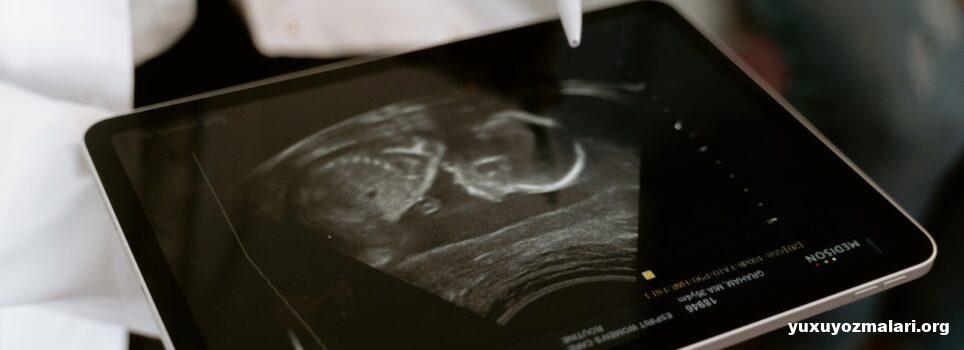

“Hamiləlik” tək hüceyrədən insan kimi mükəmməl bir orqanizmə keçidin təkrarlana bilən və müşahidə edilə bilən təkamül nümayişidir.

Hamiləlik təxminən 40 həftə davam edən bir marafondur. Aylar baxımından 9 ay, 10 gün kimi ifadə edilir. Hamiləliyin başlanğıcı da konsepsiya zamanı menstrual dövrünün ilk günüdür. Buna görə hamiləliyin ilk həftəsi əslində hələ hamilə olmadığınız bir dövrdür. Hamilə olduğunuz tarixə əsasən hesabladığınız həftə həkiminizin təyin etdiyi hamiləlik həftəsindən iki həftə geri qalır.